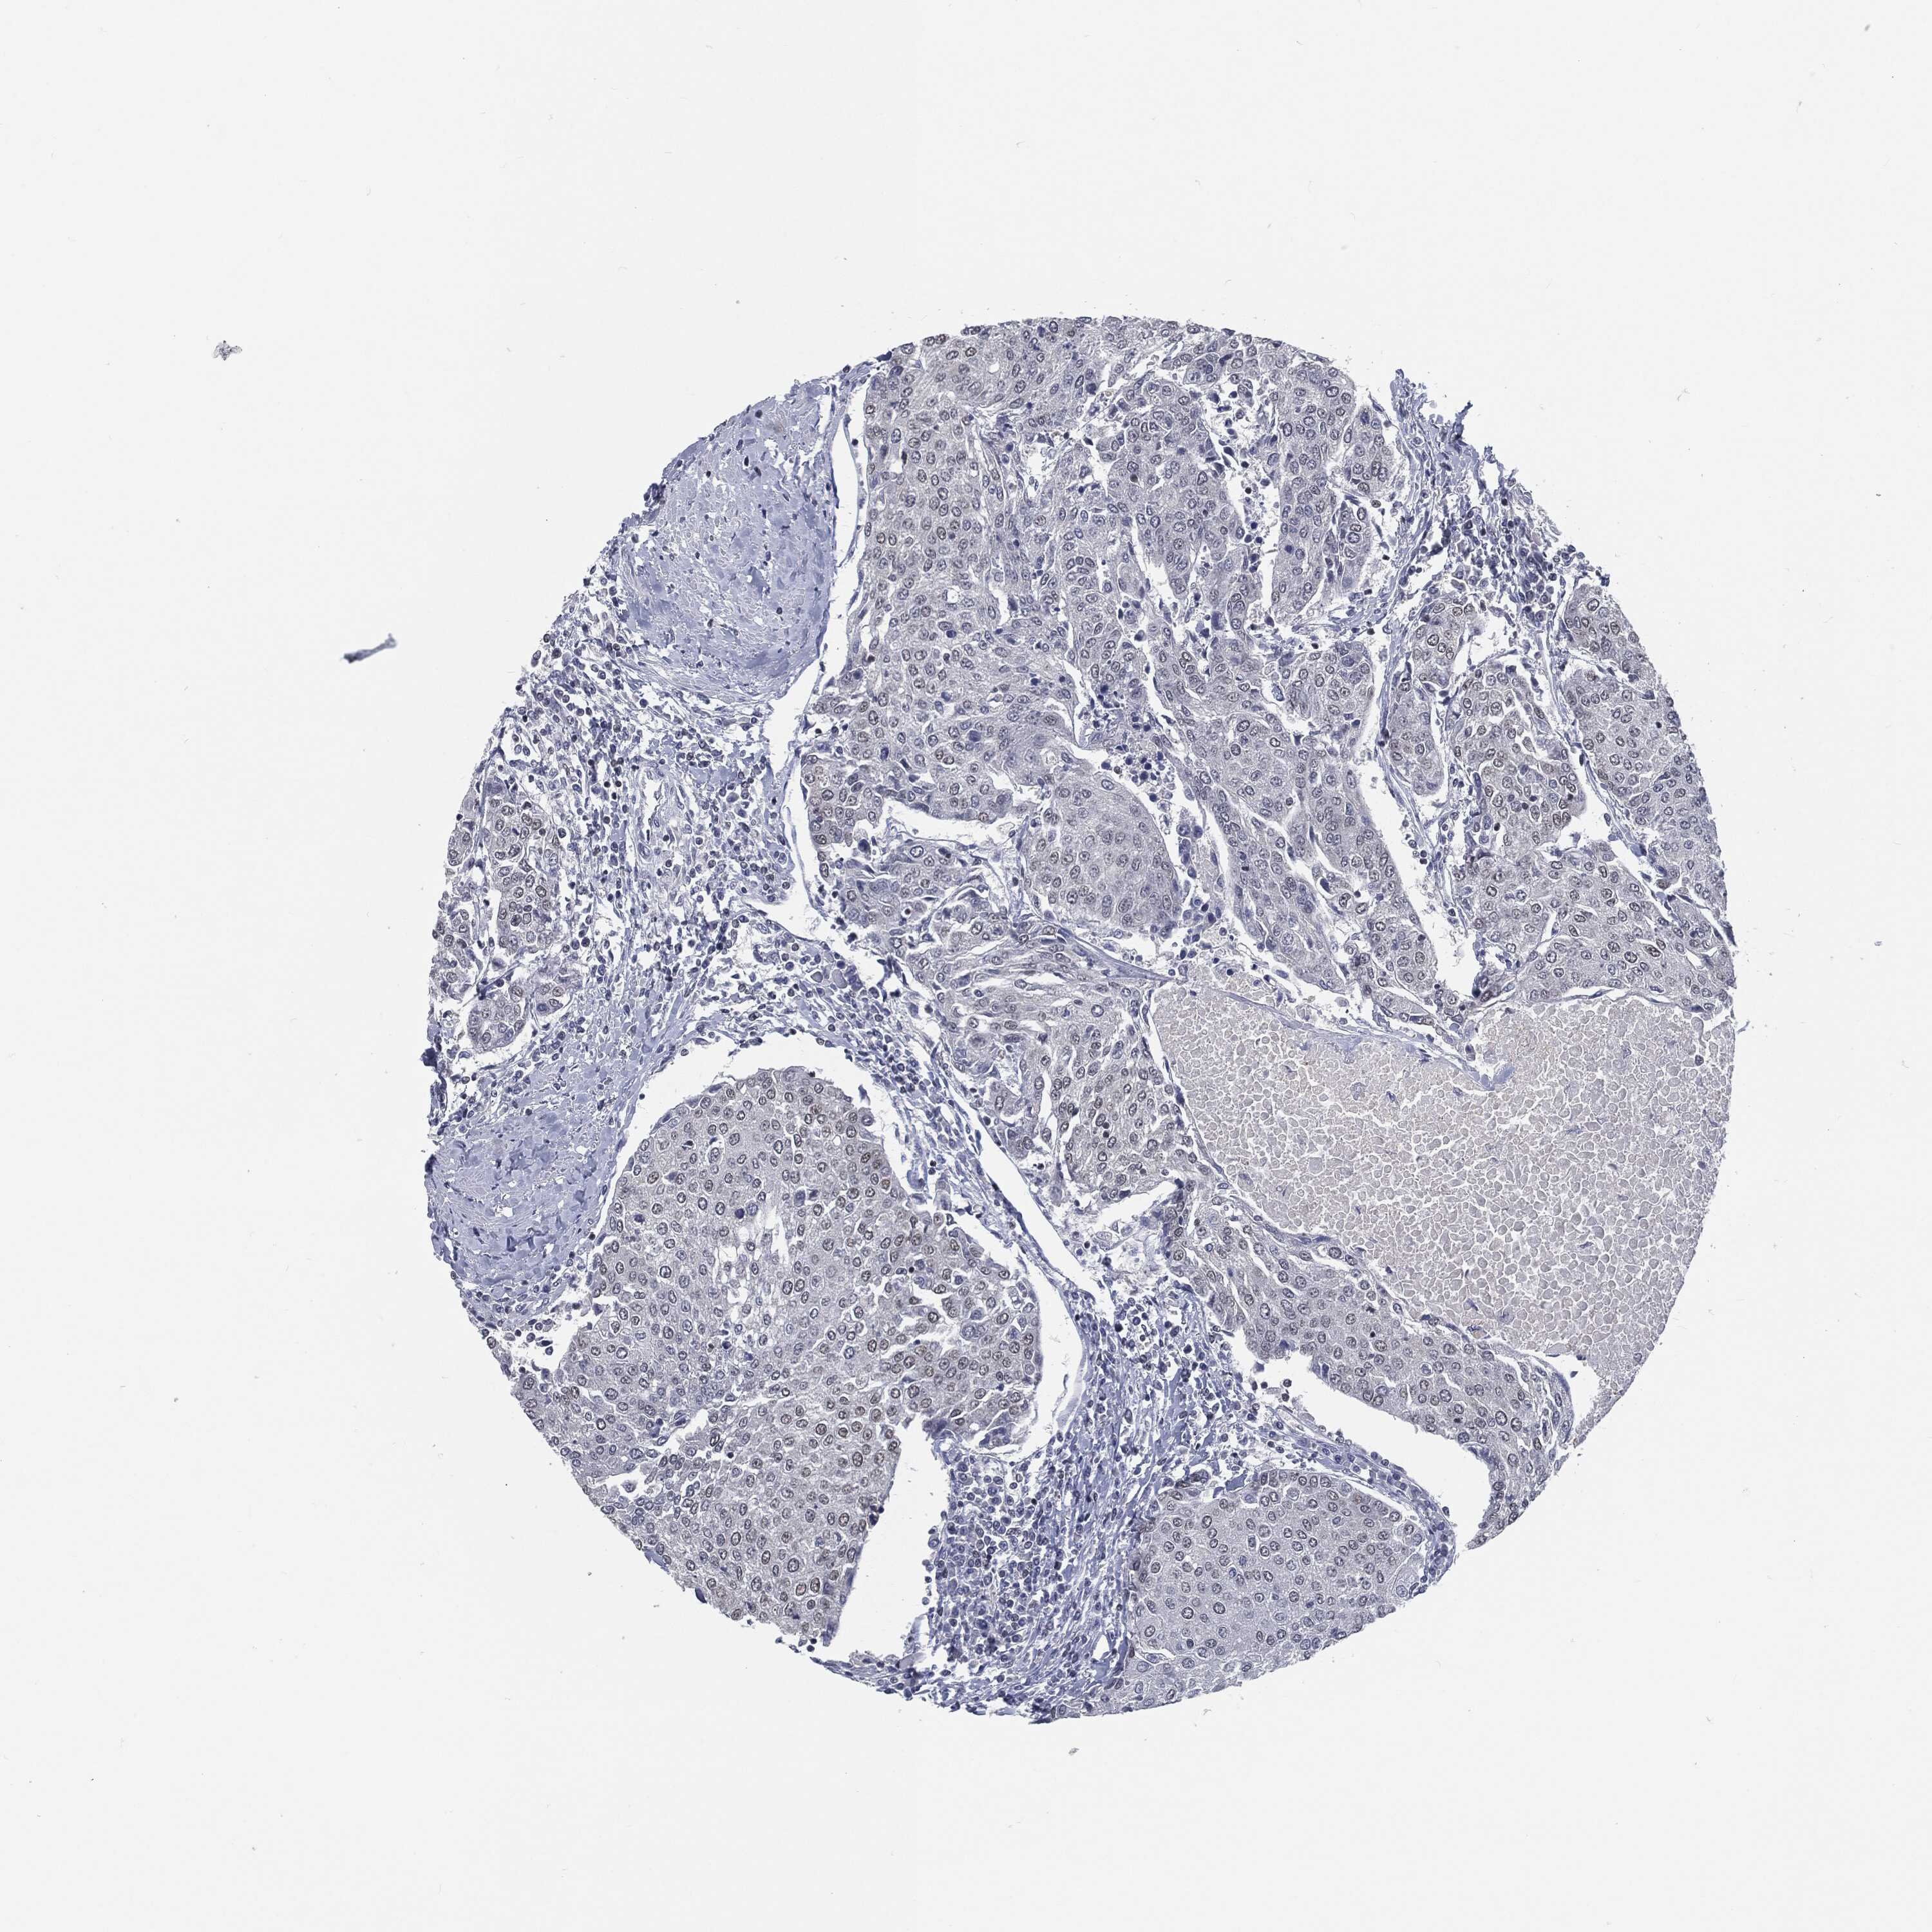

UROTHELIAL CANCER - Protein expressioni

A mouse-over function shows sample information and annotation data. Click on an image to view it in a full screen mode. Samples can be filtered based on level of antibody staining by selecting one or several of the following categories: high, medium, low and not detected. The assay and annotation is described here.

Note that samples used for immunohistochemistry by the Human Protein Atlas do not correspond to samples in the TCGA dataset.

Antibody stainingi

Antibody staining in the annotated cell types in the current human tissue is reported as not detected, low, medium, or high, based on conventional immunohistochemistry profiling in selected tissues. This score is based on the combination of the staining intensity and fraction of stained cells.

Each image is clickable and will lead to virtual microscopy that enables deeper exploration of all samples and also displays staining intensity scores, fraction scores and subcellular localization as well as patient and tissue information for each sample.

HPA011271

HPA011272

CAB013023

CAB035987

CAB058693

CAB080415

Staining

High

Medium

Low

Not detected

Intensity

Strong

Moderate

Weak

Negative

Quantity

>75%

75%-25%

<25%

None

Location

Nuclear

Cytoplasmic/membranous

Cytoplasmic/membranous,nuclear

Urothelial carcinoma, Low grade

Urothelial carcinoma, High grade

Urothelial carcinoma, NOS